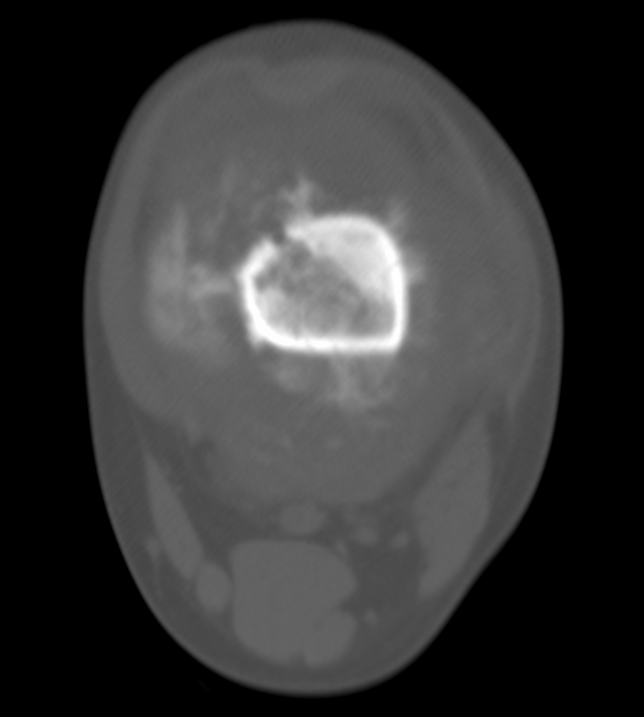

肿瘤内液-液平面多数是病灶内囊变出血所致,MRI T2W1 为上部呈高信号下部呈中低信号的液-液平面。CT 可为上部低密度下部高密度的液-液平面(图 32)。液-液平面常见于动脉瘤样骨囊肿、但也可见于骨内腱鞘囊肿(图 33)、囊性血管瘤病等其他肿瘤和肿瘤样病变。

图片

图 32.肿瘤内液-液平面:动脉瘤样骨囊肿